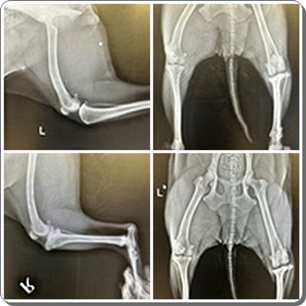

JULIET hat eine alte Fraktur, die bereits verkalkt ist.

Der Tierarzt möchte sie eigentlich nicht operieren, da er befürchtet,

dass dies eher Nachteile bringen würde.

JULIET rennt, springt und läuft ganz normal und zeigt keinerlei

Schmerzen oder Unwohlsein an.